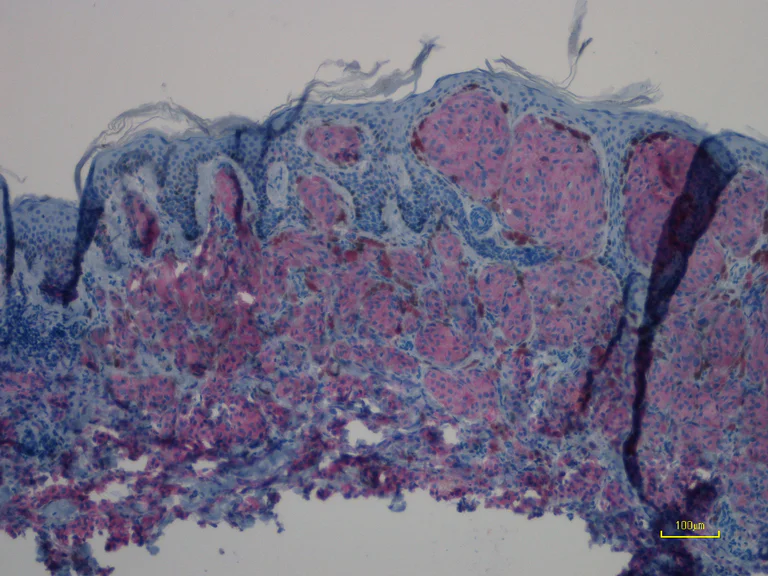

Immunohistochemical analysis of paraffin-embedded human primary malignant melanoma tissue (mutation status : NRAS Q61R) labeling NRAS with ab227658 at 1/100 dilution for 30 min at RT. The tissue was counterstained with Hematoxylin. Heat mediated antigen retrieval was achieved by using EDTA buffer pH 9.0 before IHC staining.

This image is courtesy of an anonymous collaborator.